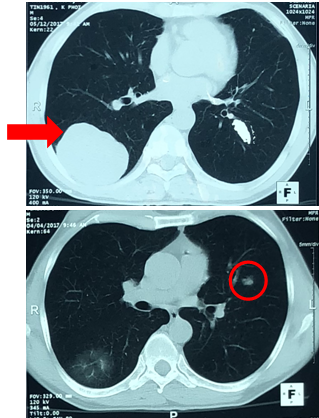

- Xạ hình xương: Không thấy tổn thương di căn xương.

Hình 4: Hình ảnh xạ hình xương toàn thân